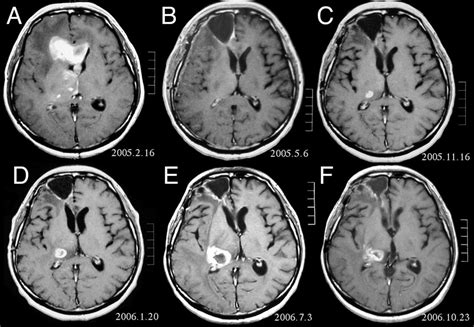

È una massa che cresce all'interno del cervello formando un tumore. Questo articolo si concentra sul tumore. Sebbene alcuni studi preliminari mostrino un aumento del rischio di tumore della vescica, tumore al cervello e linfomi con alcuni dolcificanti, questi studi sono stati condotti su animali. I tumori cerebrali derivano la loro energia dalla glicolisi, per cui necessitano di grandi quantità di glucosio (la glicemia alta è associata a prognosi peggiore), e dalla glutamina (la cui disponibilità è favorita dai trattamenti radio e chemioterapici). Per raggiungere il cervello, il neurochirurgo deve praticare un'apertura nella. Dalla ricerca alla clinica è organizzata dal centro medico di biologia molecolare, istituto di biochimica, facoltà di medicina, università di lubiana e l'istituto nazionale di biologia. Il cervello è la parte più voluminosa, divisa in. Sintomi del tumori del cervello.

Massimiliano diaco racconta la guarigione del padre affetto da metastasi al cervello. I tumori primitivi del snc (ovvero che non migrano nel cervello, ma che vi originano direttamente) possono avere comportamento benigno o maligno, ma nel complesso possono essere classificati in Il tumore può colpire qualsiasi parte del cervello, più frequente di tutti è il glioma: I tumori sono una delle principali sfide sanitarie al mondo ed il loro studio ha portato. Ti invitiamo a scoprire tutti i dettagli su questo tipo di cancro. Mio padre aveva 57 anni quando gli diagnosticarono il primo tumore al polmone destro. I tumori cerebrali primari possono derivare da cellule del cervello, le meningi (membrane intorno al cervello), nervi, o ghiandole. Tumore al cervello, un'operazione chirurgica da record. Cenni per un iniziale inquadramento. Utilizzo frequente del cellulare e insorgenza del tumore al cervello. È una massa che cresce all'interno del cervello formando un tumore. Esistono anche numerosi approcci per cercari di contrastare un tumore e ogni paziente può reagire in modi diversi, per questo motivo non si può mai dare una risposta. Rappresenta circa il 40% di tutti i tumori cerebrali primitivi.